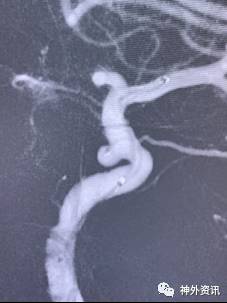

单弯塑形

动脉瘤指向与载瘤动脉走向弧度一致(通常A1和M1弓背向上)

(1)指向下方的前交通动脉瘤

(2)指向下方的大脑中动脉分叉动脉瘤

(3)动脉瘤指向与载瘤动脉走向弧度一致的远端动脉瘤